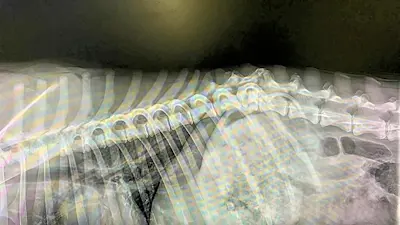

Endlich war es soweit und Lordina konnte am 24.04.24 zum Röntgen in die Klinik gebracht werden.

Die Bilder erbrachten einen eindeutigen Befund: die Wirbelsäule von Lordina ist gebrochen.

Es grenzt also an ein Wunder, dass wichtige Nerven nicht schwer verletzt bzw. durchtrennt wurden und sich Lordina nach dem schweren Trauma durch die kompetente Behandlung der Tierärzte im rifugio wieder soweit erholen konnte, dass sie zumindest selbständig gehen kann.

Für den weiteren Verlauf bedeutet dies, dass sich Lordina nun auch die nächsten Wochen nicht viel bewegen darf, also solange, bis sich ausreichend Kallus gebildet und sich die Wirbelsäule in ihrer jetzigen Position dadurch gefestigt hat. Eine Operation wird nicht notwendig sein.